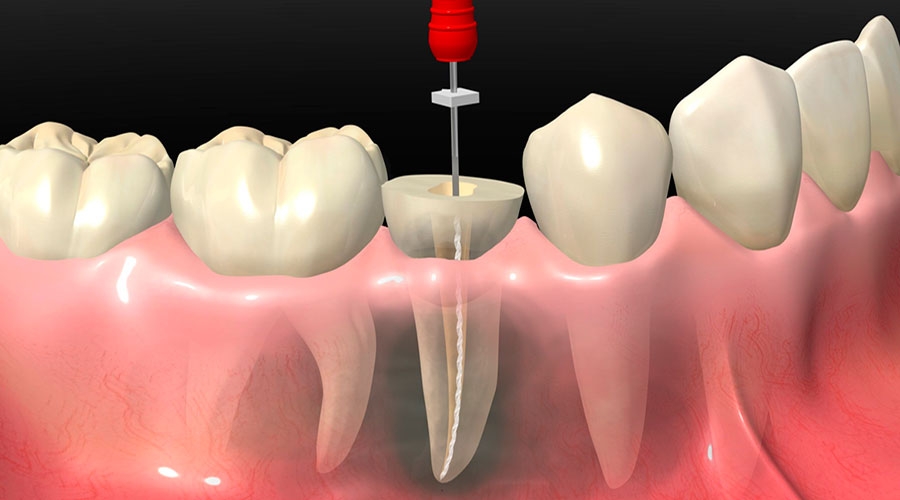

Para dentes com grande destruição da estrutura, fraturas, hipersensibilidade ou exposição da polpa, onde há a possibilidade de serem utilizados em uma reabilitação protética.

Tratamento de canal